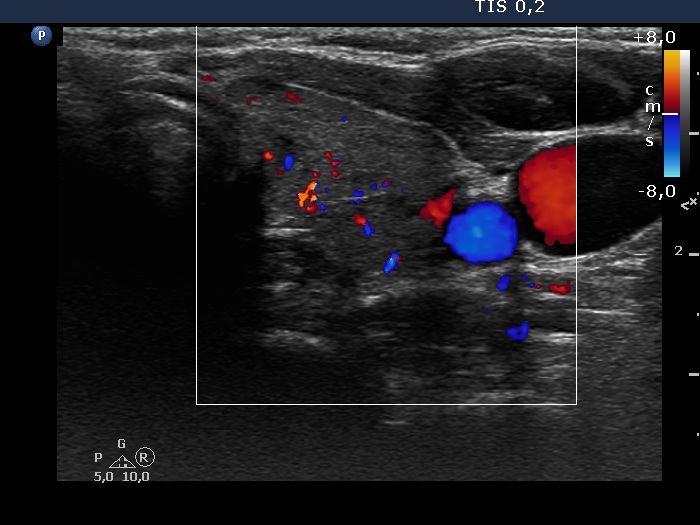

Consecutive patients with the final diagnosis of Hashimoto's thyroiditis - case 12 (881) (ultrasonographic picture 5)

Right lobe, transverse scan, color Doppler mode. The vascularization is not specific.